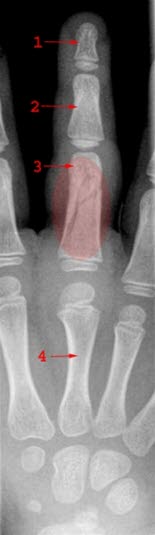

Et bein i fingeren kalles på fagspråket en falang. Bortsett fra tommelen består en finger av tre falanger - den innerste falangen (proksimale falang eller grunnfalangen), den midtre falangen (mellom-falang) og den ytre falangen (distale falang). Tommelen består av to bein.

En finger har tre ledd - innerst et ledd mellom proksimale falang og et bein (metakarp) i mellomhånden (MCP-leddet, metacarpophalangeal-leddet), dernest ledd mellom proksimale og midtre falang (PIP-leddet, proximale interphalangeal-ledd) og ytterst ledd mellom midtre og distale falang (DIP-leddet, distale interphalangeal-ledd).